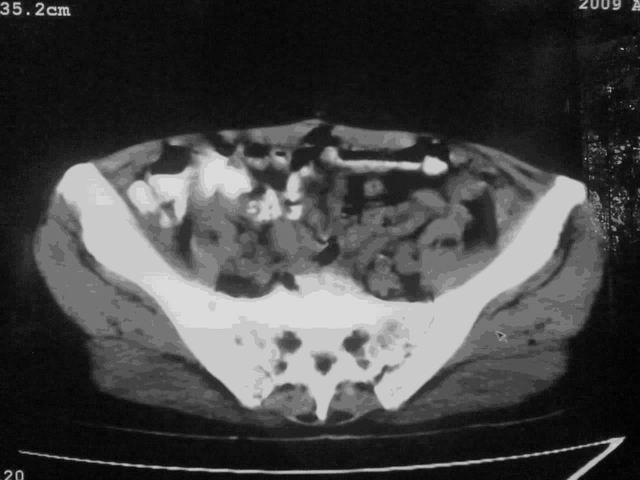

好象是横结肠占位肝转移,胰头占位?【伙计,您的片也真够意思】

伪影太多,考虑降结肠癌伴肝转移,胆囊炎

伪影太多,考虑升结肠癌伴肝转移,胆囊炎

片子质量差了点,好像是降结肠

伪影太多,考虑降结肠癌伴肝转移,胆囊炎。